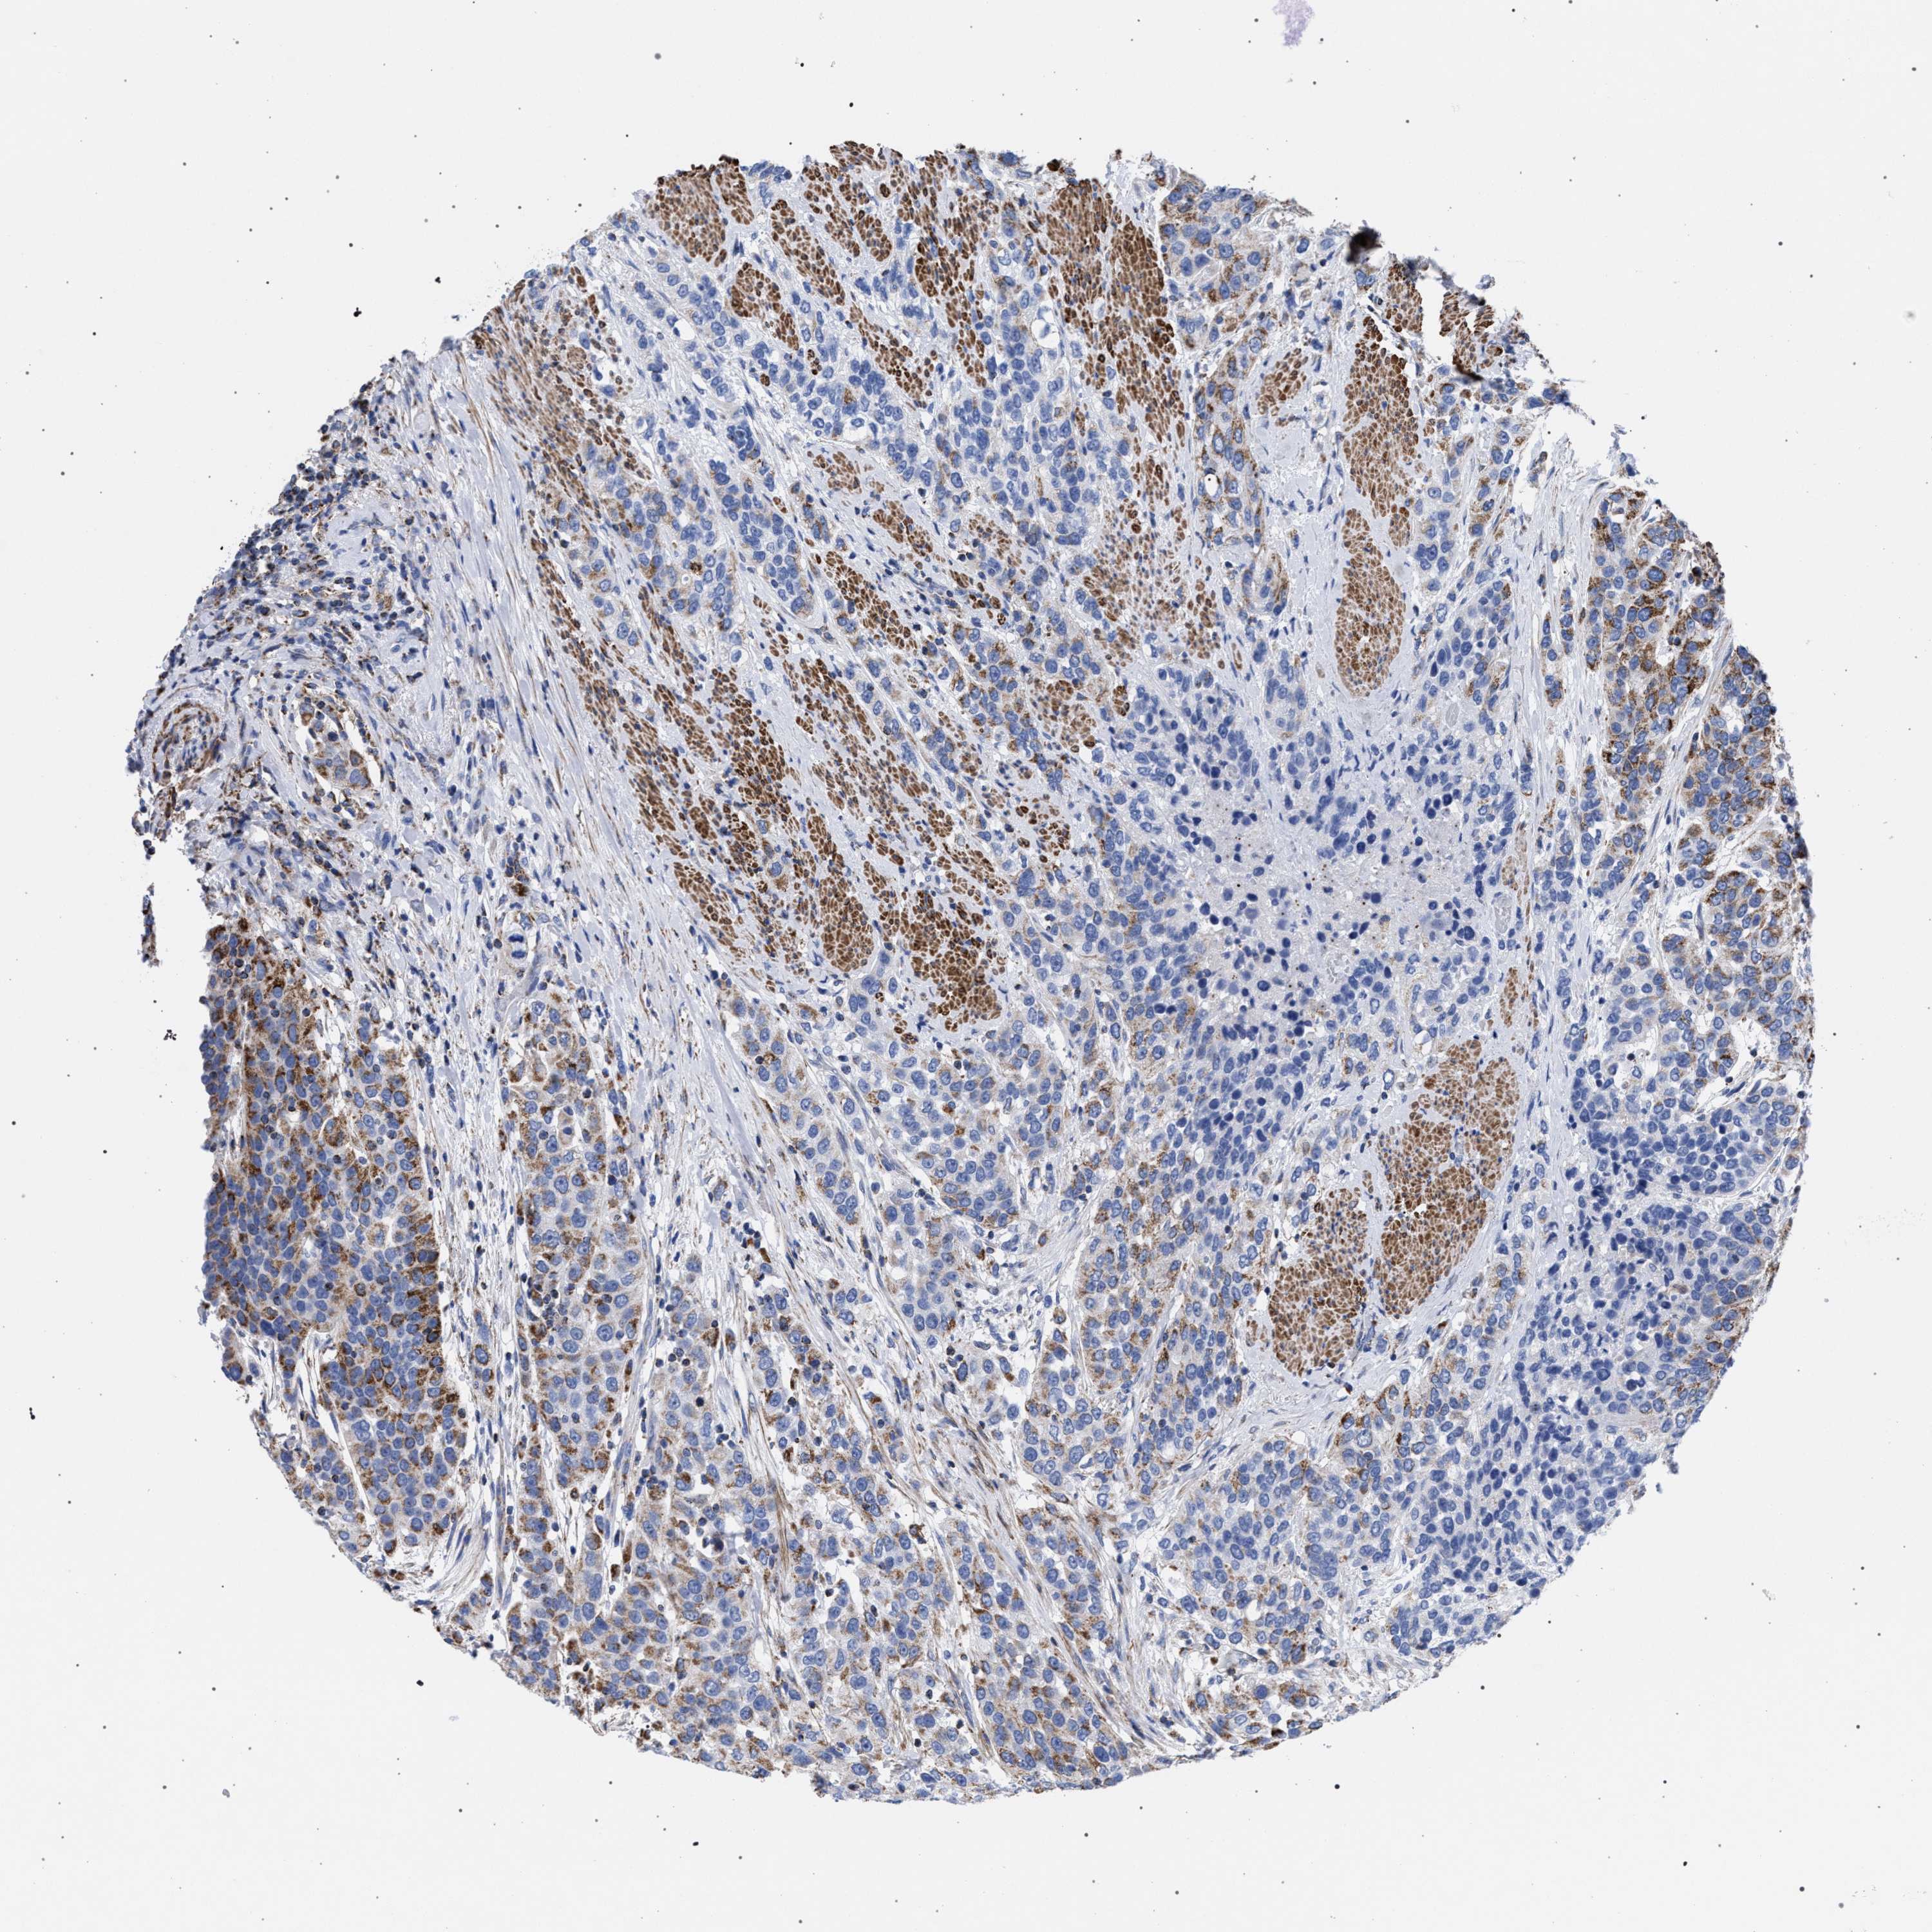

UROTHELIAL CANCER - Protein expressioni

A mouse-over function shows sample information and annotation data. Click on an image to view it in a full screen mode. Samples can be filtered based on level of antibody staining by selecting one or several of the following categories: high, medium, low and not detected. The assay and annotation is described here.

Antibody stainingi

Antibody staining in the annotated cell types in the current human tissue is reported as not detected, low, medium, or high, based on conventional immunohistochemistry profiling in selected tissues. This score is based on the combination of the staining intensity and fraction of stained cells.

Each image is clickable and will lead to virtual microscopy that enables deeper exploration of all samples and also displays staining intensity scores, fraction scores and subcellular localization as well as patient and tissue information for each sample.

Antibody HPA022271

Antibody CAB019284

Staining

High

Medium

Low

Not detected

Intensity

Strong

Moderate

Weak

Negative

Quantity

>75%

75%-25%

<25%

None

Location

Nuclear

Cytoplasmic/membranous

Cytoplasmic/membranous,nuclear

Urothelial carcinoma, Low grade

Urothelial carcinoma, High grade